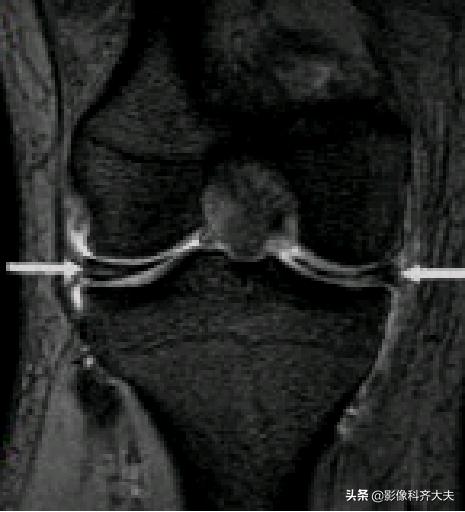

后股板韧带:

内侧半月板后角上隐窝: